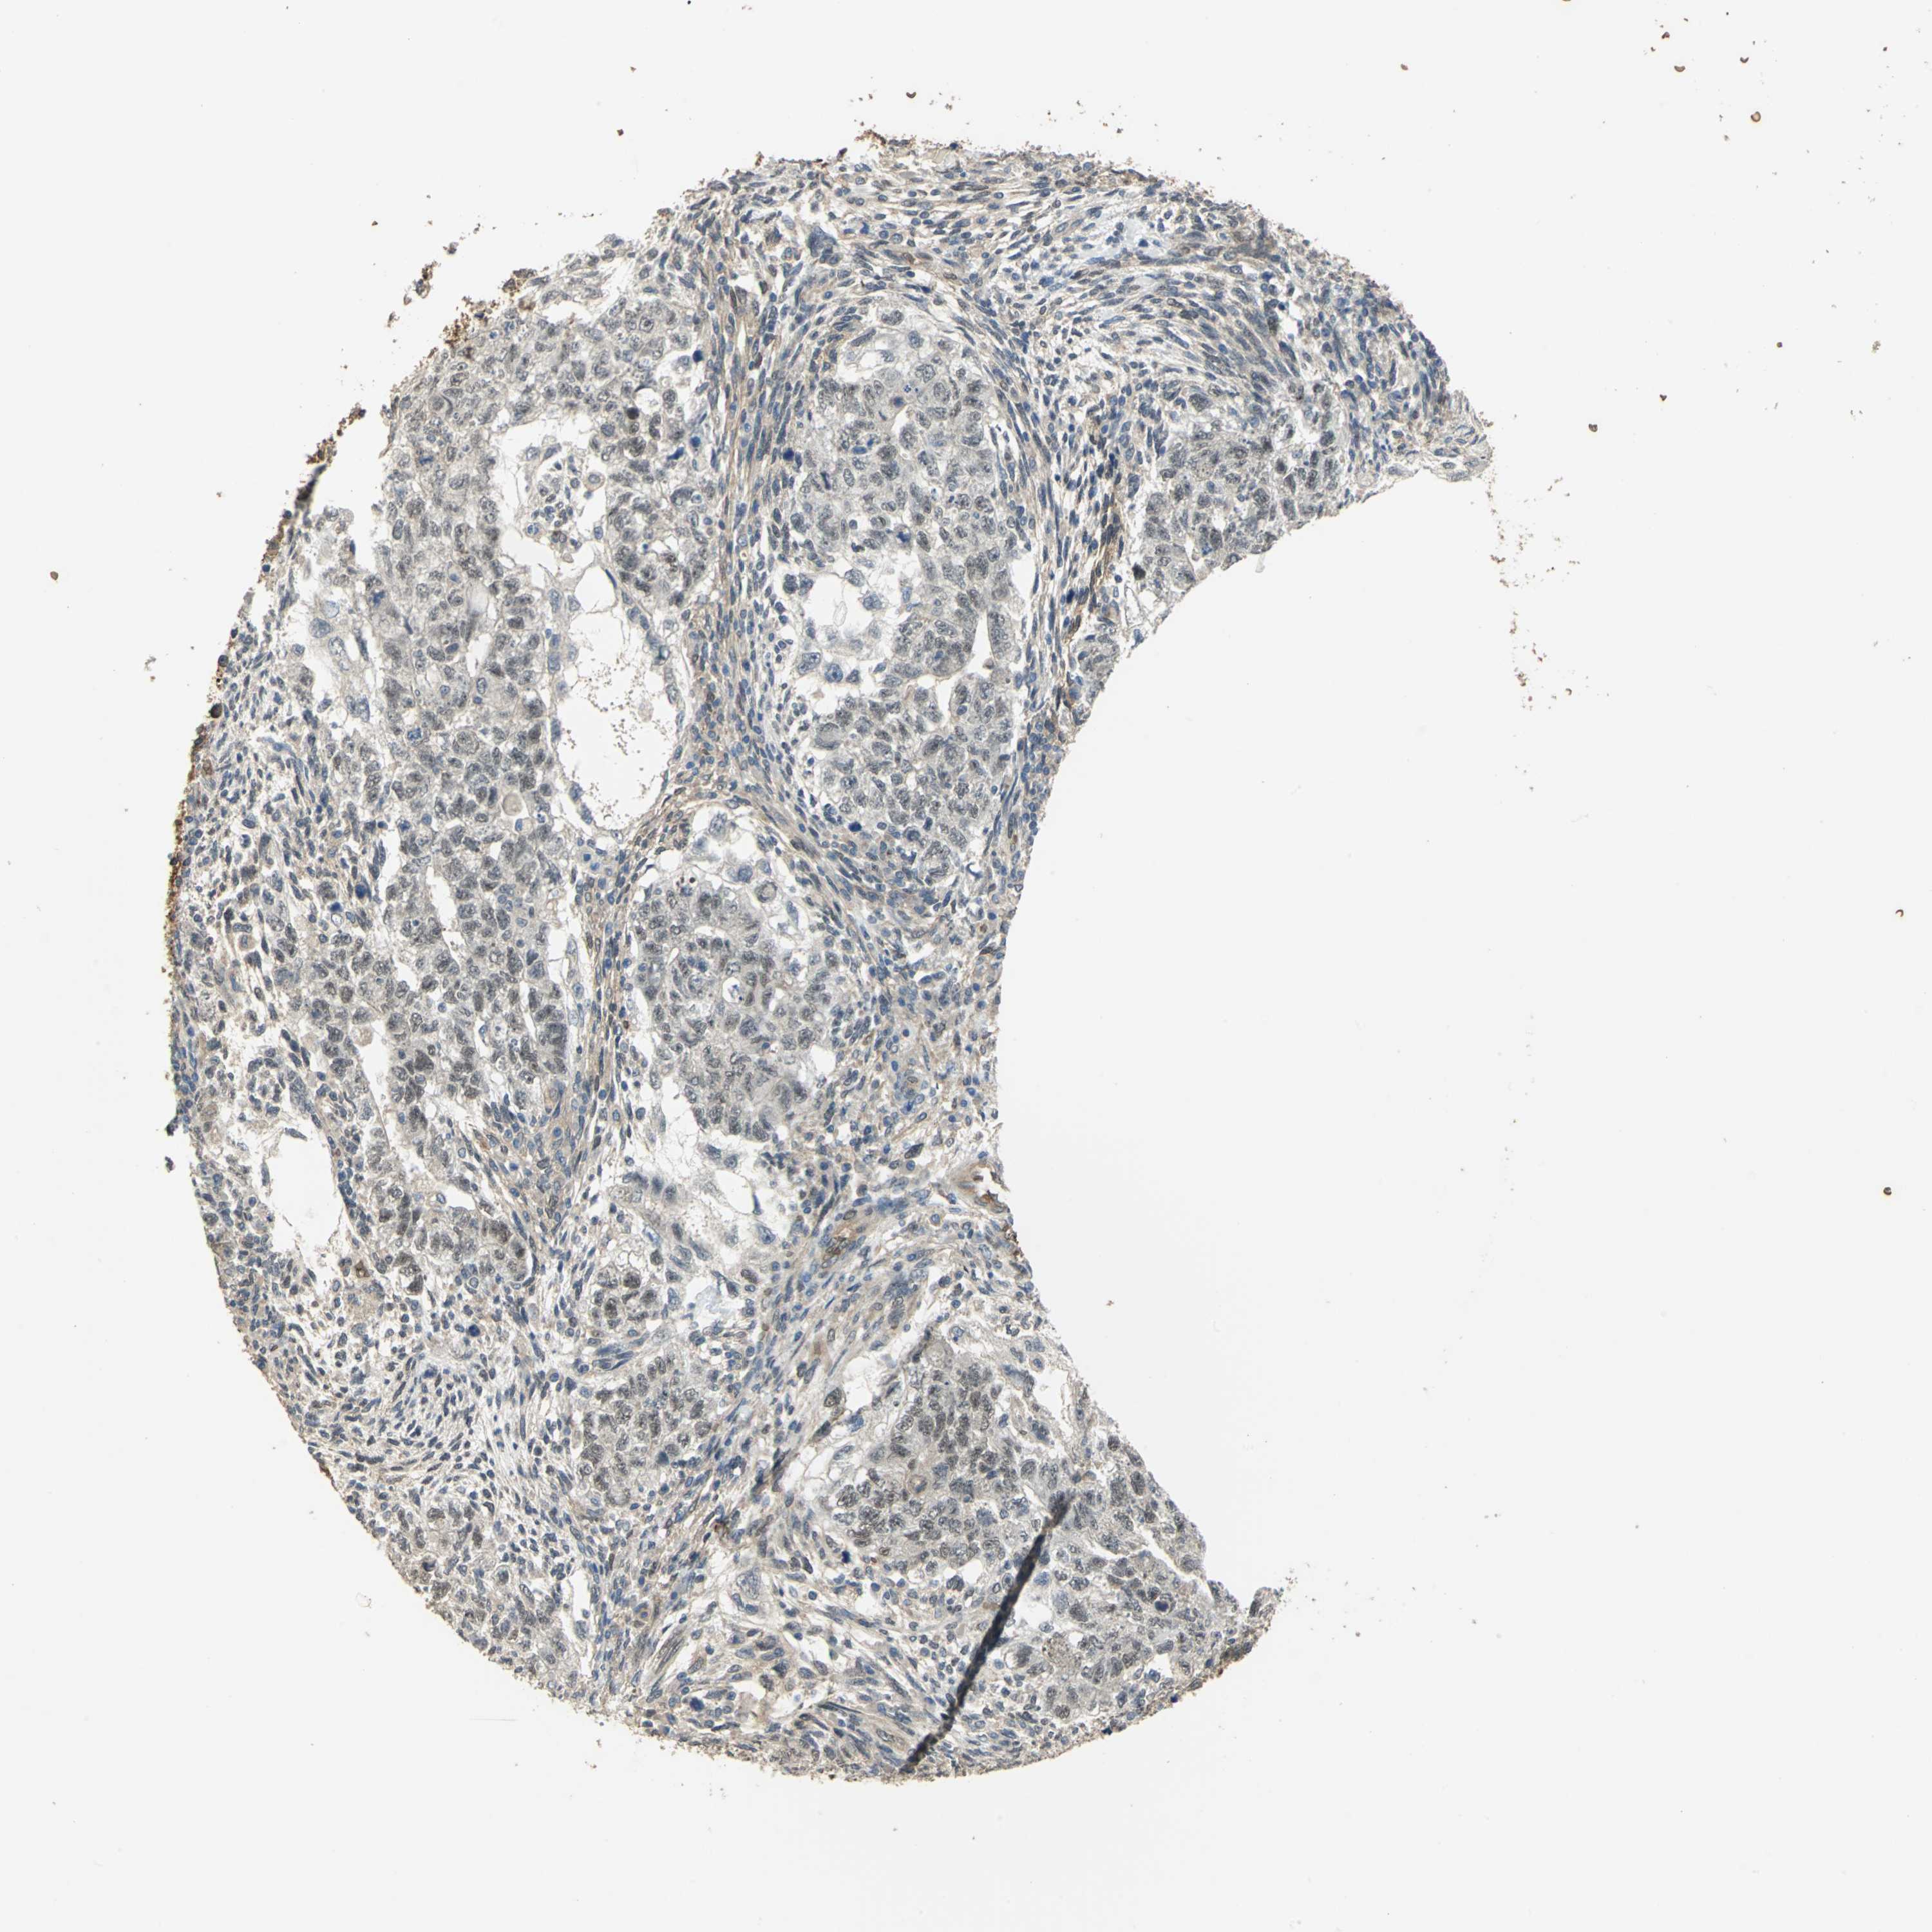

TESTIS CANCER - Protein expressioni

A mouse-over function shows sample information and annotation data. Click on an image to view it in a full screen mode. Samples can be filtered based on level of antibody staining by selecting one or several of the following categories: high, medium, low and not detected. The assay and annotation is described here.

Note that samples used for immunohistochemistry by the Human Protein Atlas do not correspond to samples in the TCGA dataset.

Antibody stainingi

Antibody staining in the annotated cell types in the current human tissue is reported as not detected, low, medium, or high, based on conventional immunohistochemistry profiling in selected tissues. This score is based on the combination of the staining intensity and fraction of stained cells.

Each image is clickable and will lead to virtual microscopy that enables deeper exploration of all samples and also displays staining intensity scores, fraction scores and subcellular localization as well as patient and tissue information for each sample.

Antibody HPA006308

Carcinoma, Embryonal, NOS

Seminoma, NOS